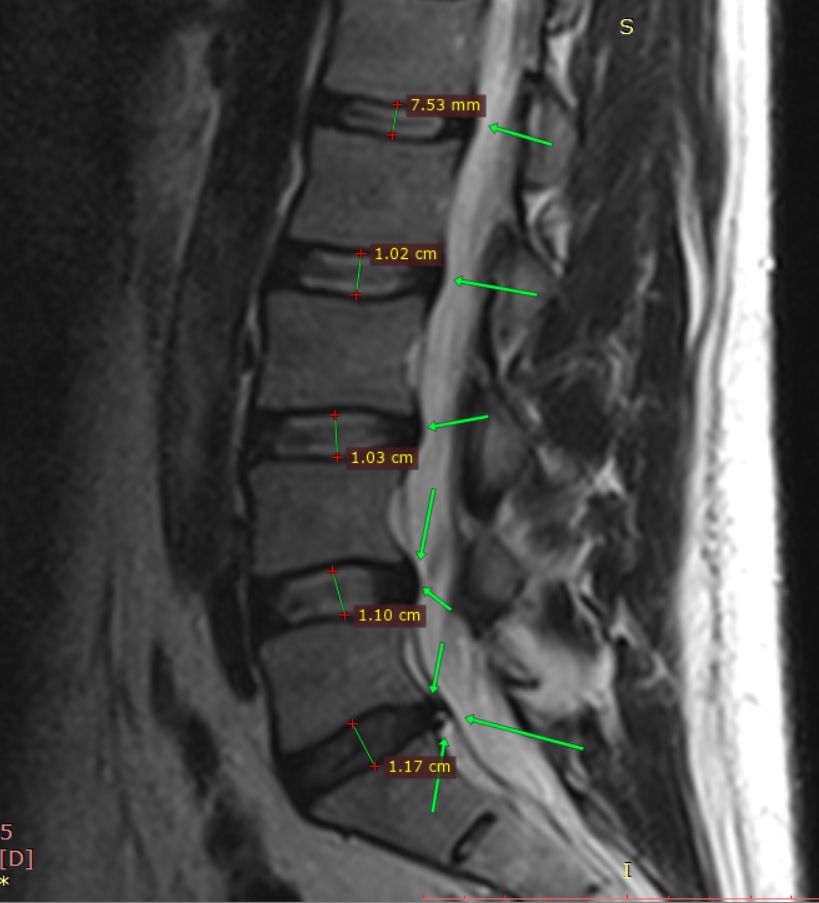

MMRLANDRYGGMR2025112911433542.png

>>328965575 (OP)

Хуйня у тебя, а не грыжа. Зацени мою:

L5 / L5 11 мм. Осенью боль была такая, что аж морфин прописывали и тот не до конца снимал. Теперь мне упражнения всю жизнь делать. Если все окей, то войду в ремиссию и опять буду и на веле и на лыжах горных катать. А пока работаю большую часть дня стоя, чтобы спину не нагружать. Хорошо, что и в офисе и дома столы с электро лифтом